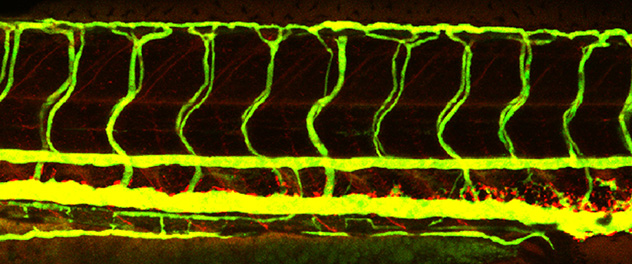

A zebrafish embryo used in vascular permeability studies Investigating disease mechanisms

This zebrafish model is one example of our lab's efforts to learn more about how vascular changes contribute to a range of diseases and conditions.

• Cerebrovascular disease and brain health. Our research explores how blood-brain barrier dysfunction and vascular changes contribute to aging and neurodegenerative conditions such as Alzheimer's disease. We use zebrafish and other models for real-time vascular imaging.